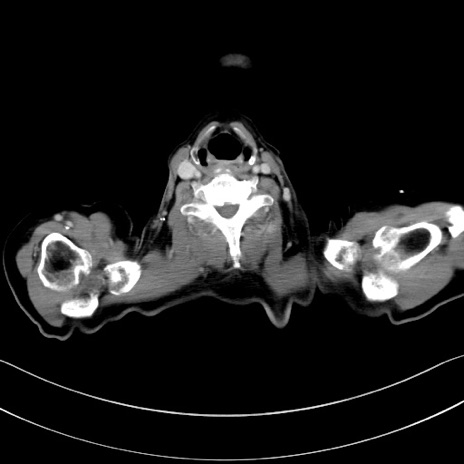

症例28(横断像)

【症例】60歳代男性

【主訴】嘔吐

【現病歴】胃癌にて胃全摘後。食思不振が悪化し、夜中に嘔吐することがある。

【既往歴】胃癌、胃全摘、脾摘、胆摘後

【データ】WBC 5900、CRP 10.56